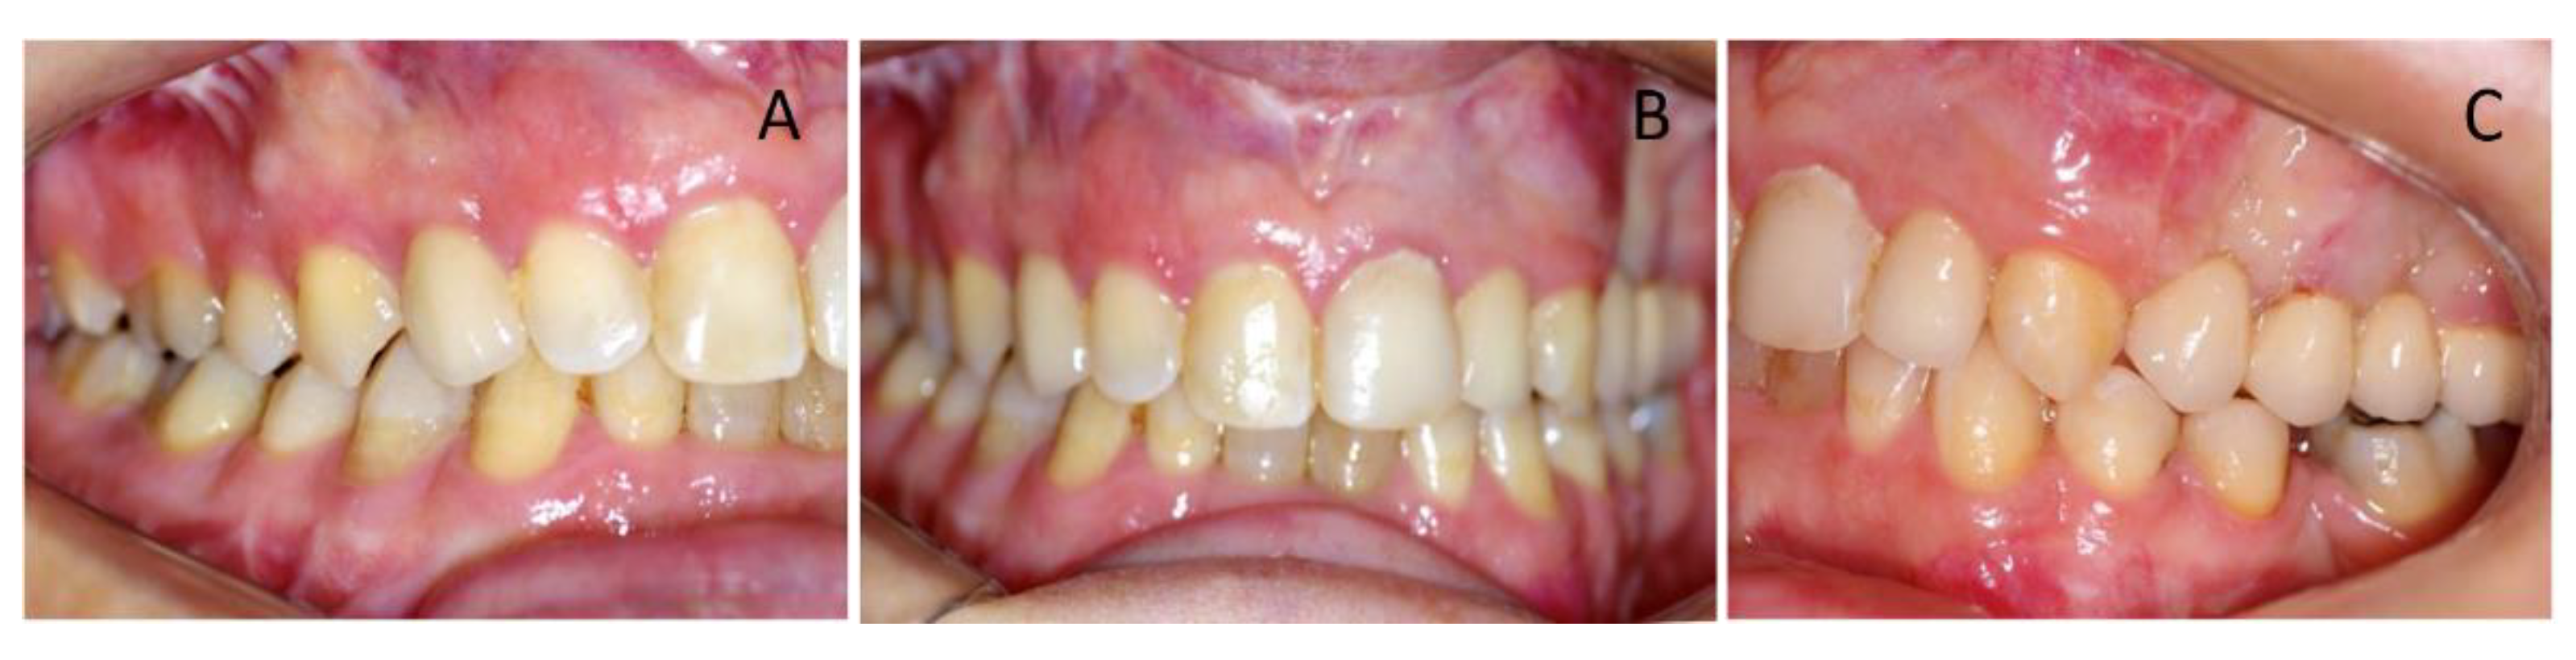

Clinical oral examination revealed dentition with numerous missing teeth (Table 1 and Figure 2), and the panoramic radiograph showed radiculomegaly in the upper right central incisor, upper left canine, first lower left premolar, lower right and left canine, lower right central incisor, lower left central incisor, lower right lateral incisor, and first lower right and left premolar.

Figure 2. Pre-treatment, intra-oral photographs of patient showing right (A), frontal (B), and left occlusion (C). Note the missing teeth, gummy smile, and severe malocclusion.